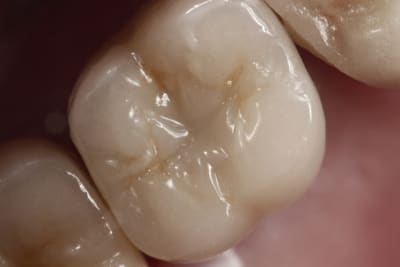

Exemple ici d'un cas ant avec

- une facette

- une ccm sur moignon metal implantaire

- une ccm sur inlay core

- une ccm a tenon.